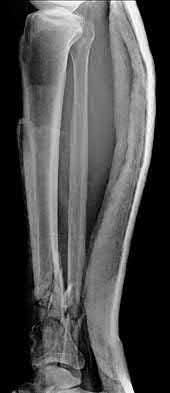

4. # After undergoing the treatment seen in Figure A, when should a patient be expected to safely operate the brakes of an automobile?

Corrent answer: 4

Figure A shows a patient after an open reduction and internal fixation of a bimalleolar ankle fracture.

Egol et al showed that by nine weeks, the total braking time of patients who had undergone fixation of a displaced right ankle fracture returns to the normal, baseline value.

Egol et al, also found that appropriate braking time returns at a point 6 weeks after initiation of weightbearing after treatment of lower extremity long bone and periarticular fractures, as examined with a driving simulator. No differences were seen in return of braking time between periarticular fractures and long bone injuries.